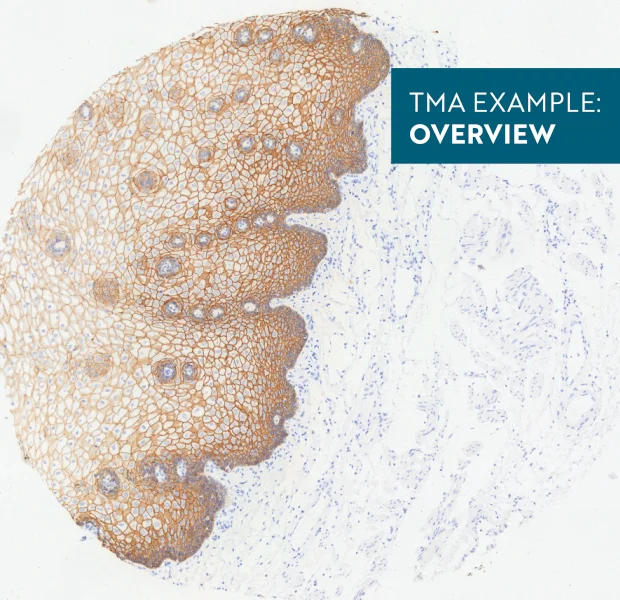

Tissue microarray (TMA) analysis demonstrates automated detection of nuclei, epithelial cells, and membranes, combined with machine learning–based tissue classification and spatial analysis of immune cells.

Tissue microarrays (TMAs) have proven themselves as a standard molecular clinical diagnosis technique. TMAs are paraffin blocks in which up to 1000 individual tissue cores assembled in array fashion, allowing high-throughput histological analysis.

The TissueFAXS platform including the high-end image analysis solution StrataQuest provides specific workflow to scan and analyze the TMA samples containing multiple regions on one slide. TMA analysis in StrataQuest is available for images acquired in all imaging modalities (multispectral, fluorescence, brightfield).

In the first example, StrataQuest was utilized to analyze a TMA sample stained for hematoxylin (blue) and for E-cadherin present in the cell membranes of epithelial cells (brown). On the original image (a), E-cadherin is shown in brown and nuclei in blue. The aim was to detect the nuclei, the epithelial cells and the membranes of epithelial cells. The challenge with this analysis was that some cells do not contain nuclei.